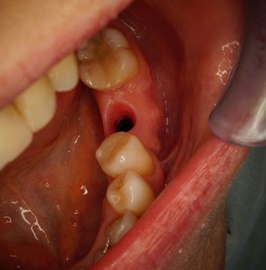

Przypadek odbudowy zębów trzonowych z początkowymi znacznymi zanikami kości. Odbudowa kości pionowa i pozioma, następnie implantacja i faza protetyczna.